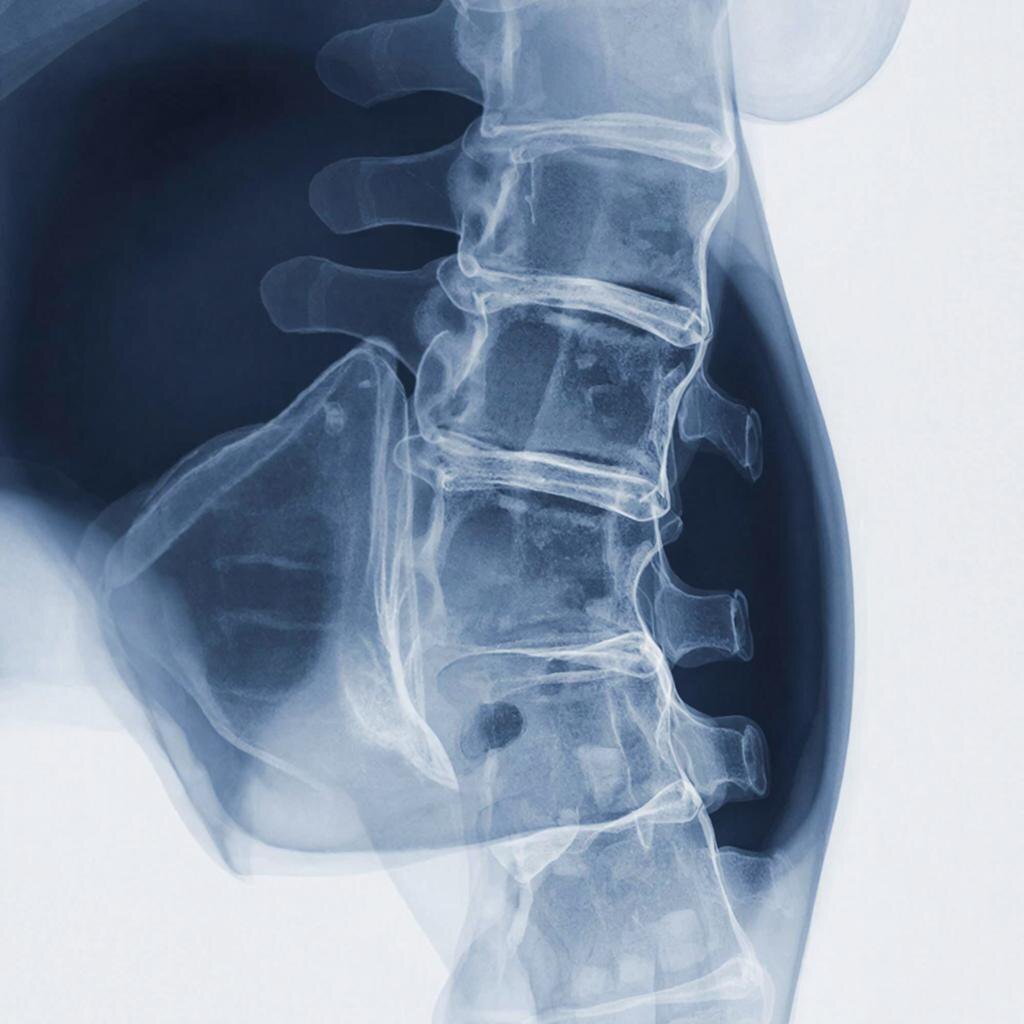

Сферические кластеры (сфероиды) смешивали с β-трикальцийфосфатом. Затем эту смесь транспортировали к позвонкам L4 и L5 у крыс с переломами позвоночника. Причиной же переломов стал остеопороз.